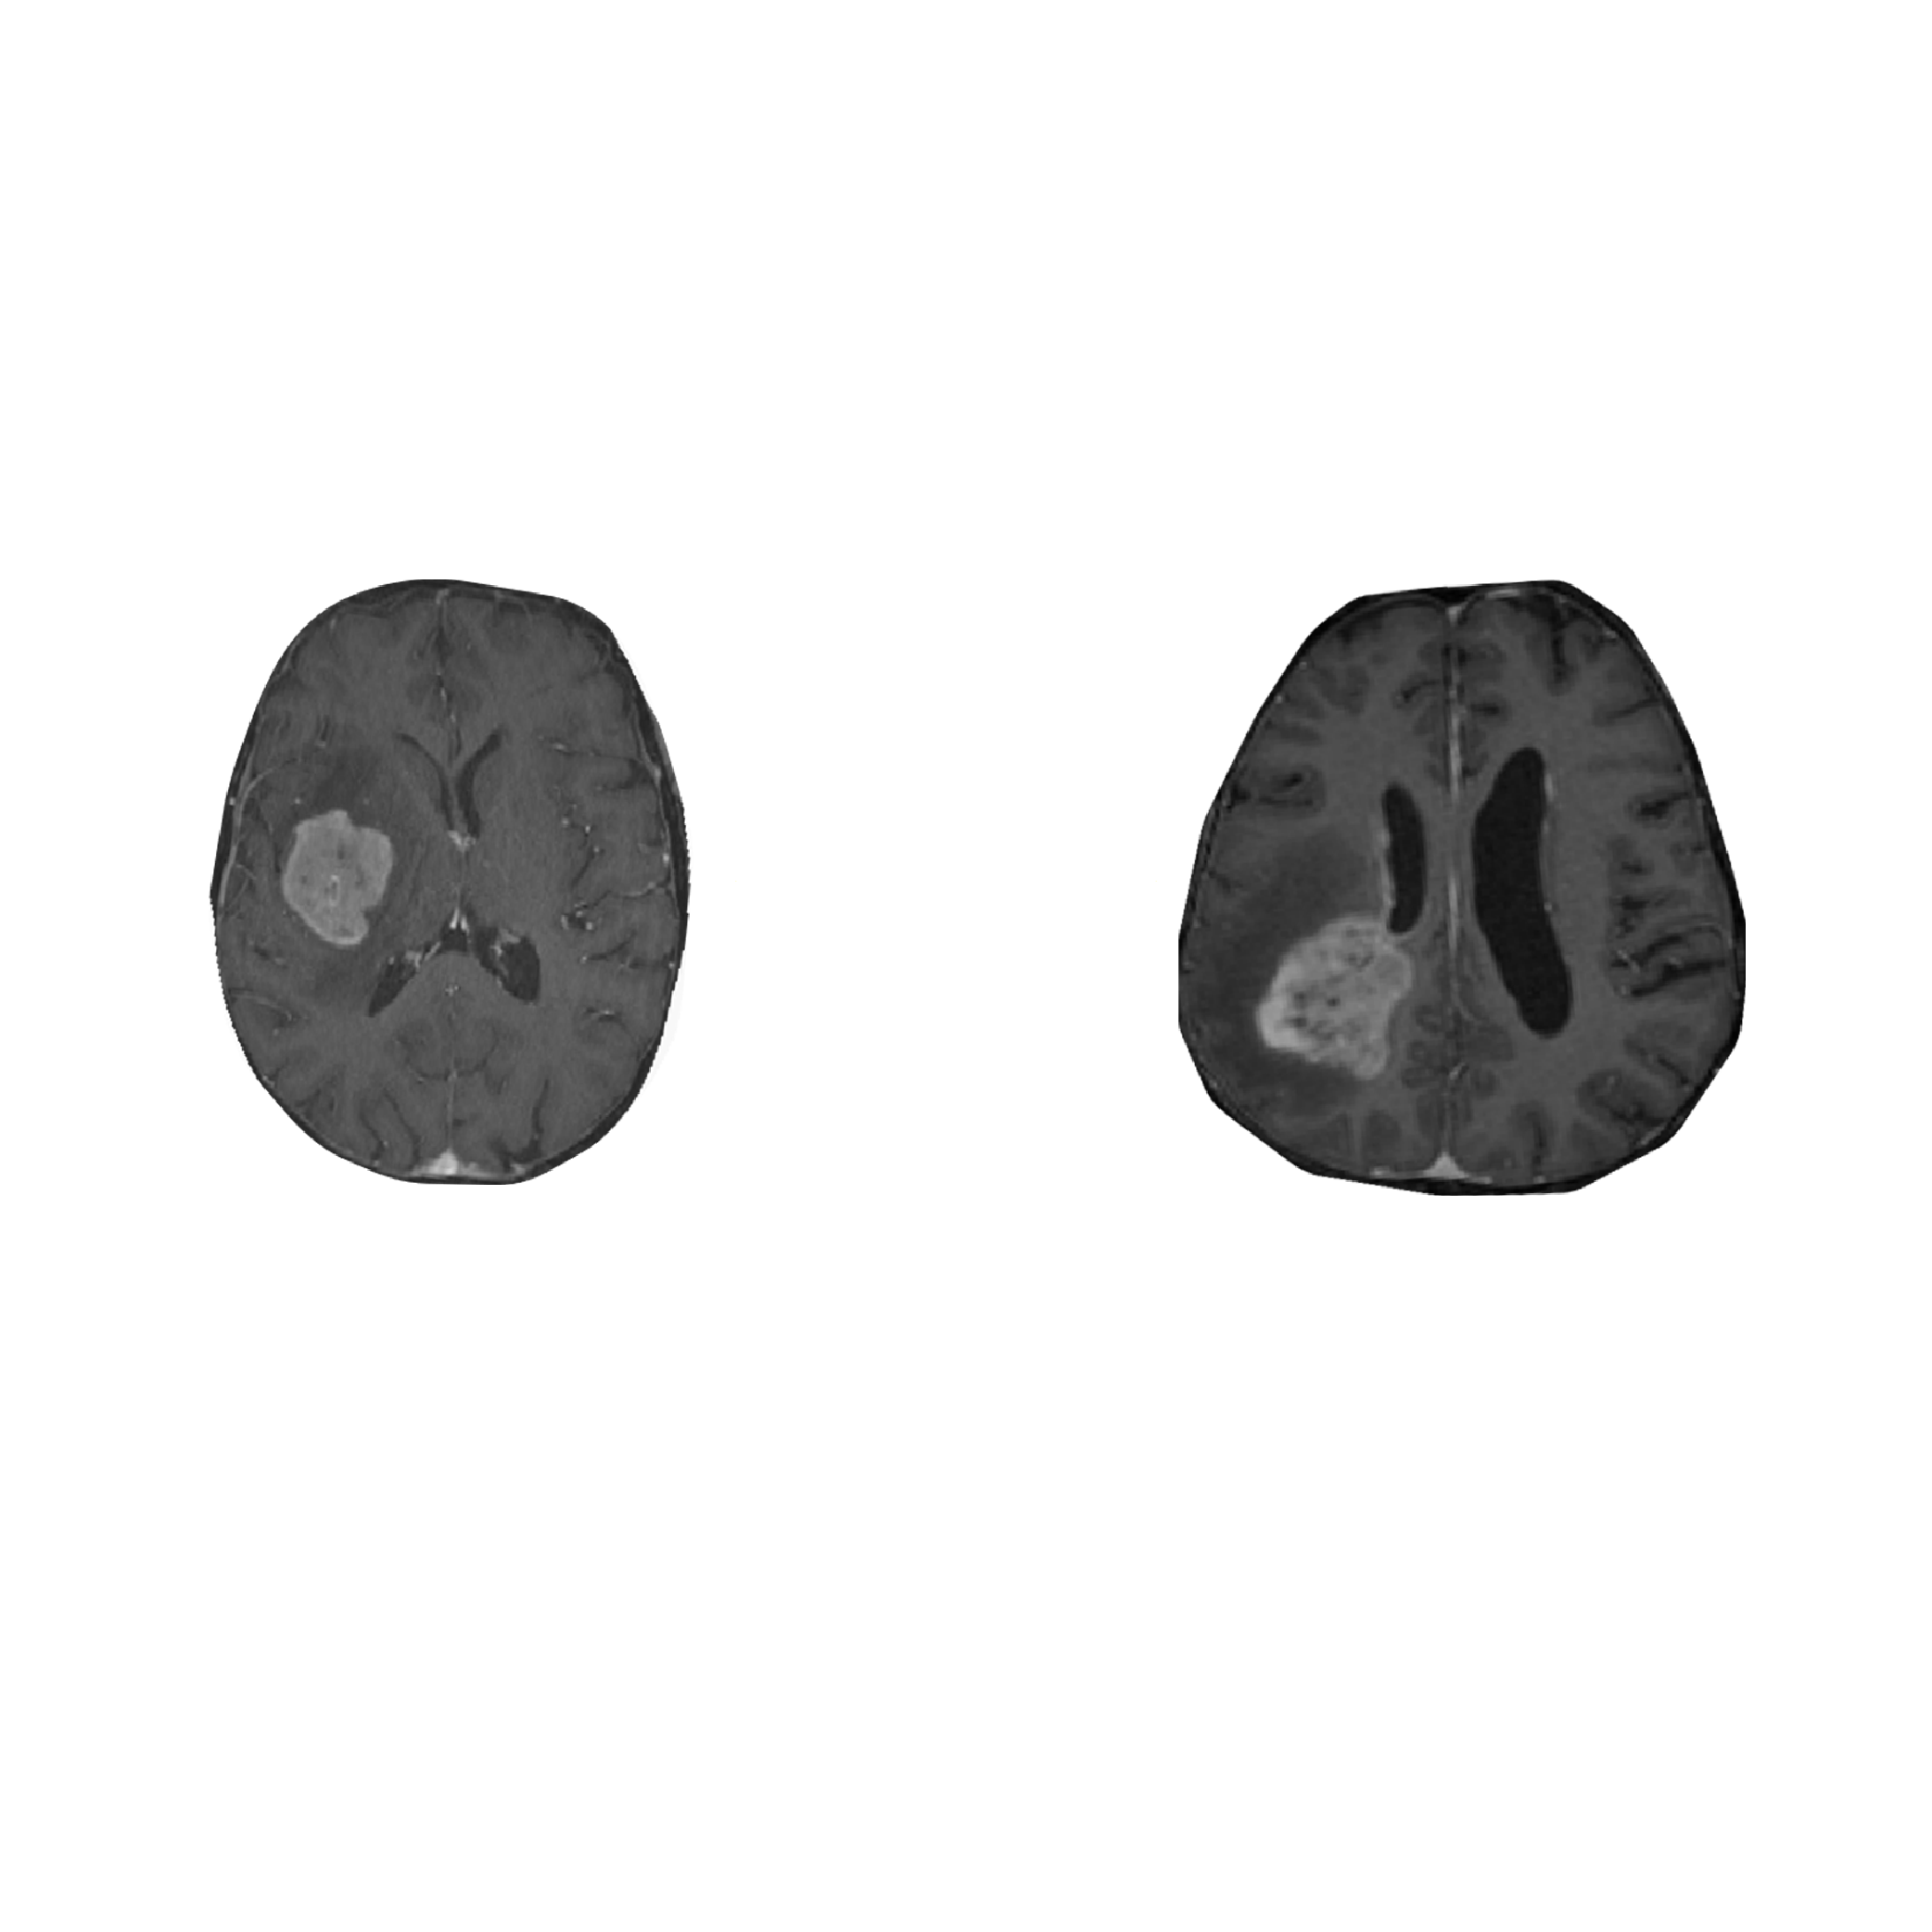

Accurately discerning primary central nervous system lymphoma (PCNSL) from glioblastoma (GBM) on preoperative MRI is hard but crucial, because early steroid use can impair PCNSL biopsy yield and delay targeted therapy. In our iScience study, we trained a DenseNet169 model on a balanced cohort (68 PCNSL, 69 GBM) using only standard sequences (T1, T1-CE, T2,…

Building on the neural network (see development), the LINNDA project translated the concept into a clinically usable workflow. Instead of replacing clinicians, LINNDA positions AI as a tie-breaker: two clinicians independently assess the MRI, and only if their diagnoses differ does the CNN provide a decision. This simple rule mirrors real-world consensus processes while keeping full…